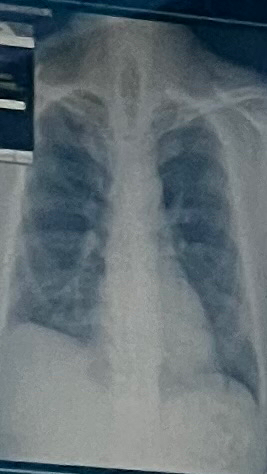

혹시이사진으로 보이는게있을까요?

늑막유착과 심비대?이넣게판정받았어요

사진이라 잘안보이시겠지만 한번봐주셔요 ㅠㅠ

그냥사진으로 찍은거에요 확실하지않겠지만 도와주세요

오른쪽 CPA blunting의 가능성은 있지만 임상 병력없이 엑스레이 사진 하나로 늑막유착을 진단하기는 어렵고 감별진단에 포함할 수는 있을 것 같습니다. 사진상에서는 심비대도 아주 도드라져 보이지는 않으나 사진의 질이 좋지 않아 판단이 어려우며 정확한 필름을 가지고 영상의학과 판독을 따르시는 것이 좋아 보입니다.